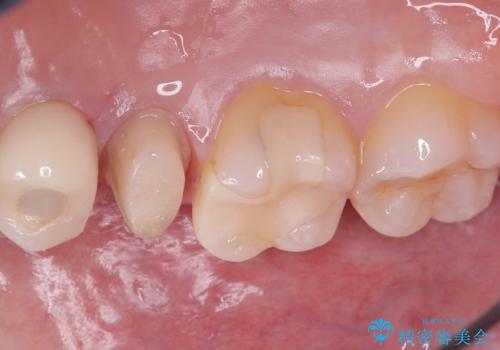

右上5番の口蓋側歯質が失われ、露出した歯質内面は軟化象牙質を除去していく過程で露髄する可能性が大きくありました。患者さんには生活歯髄療法と抜髄のどちらかになると説明し、生活歯髄療法の適応と判断し行いました。

補綴物は残存歯質量からクラウンとしました。